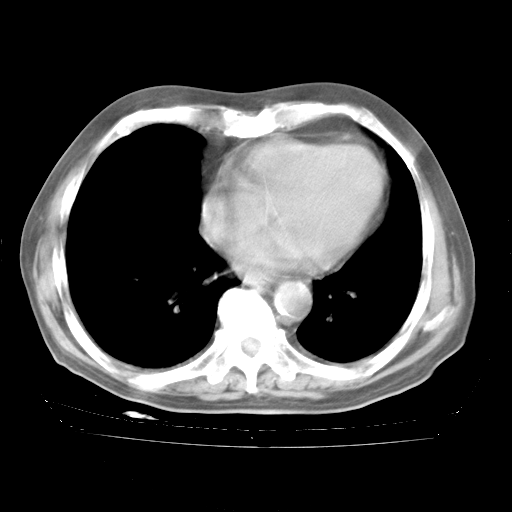

4月28日肺部CT